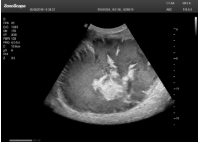

肝癌

采用了單晶體探頭材料,探頭面是凸面,接觸面小,成像視野呈扇形,應(yīng)用廣泛,常應(yīng)用于腹部、婦產(chǎn)、肺部等相對部位較深的臟器。

超聲圖像是探頭和系統(tǒng)平臺(tái)緊密結(jié)合的產(chǎn)物,因此在同一臺(tái)機(jī)器上,軟件、硬件都需要達(dá)到單晶探頭的要求。